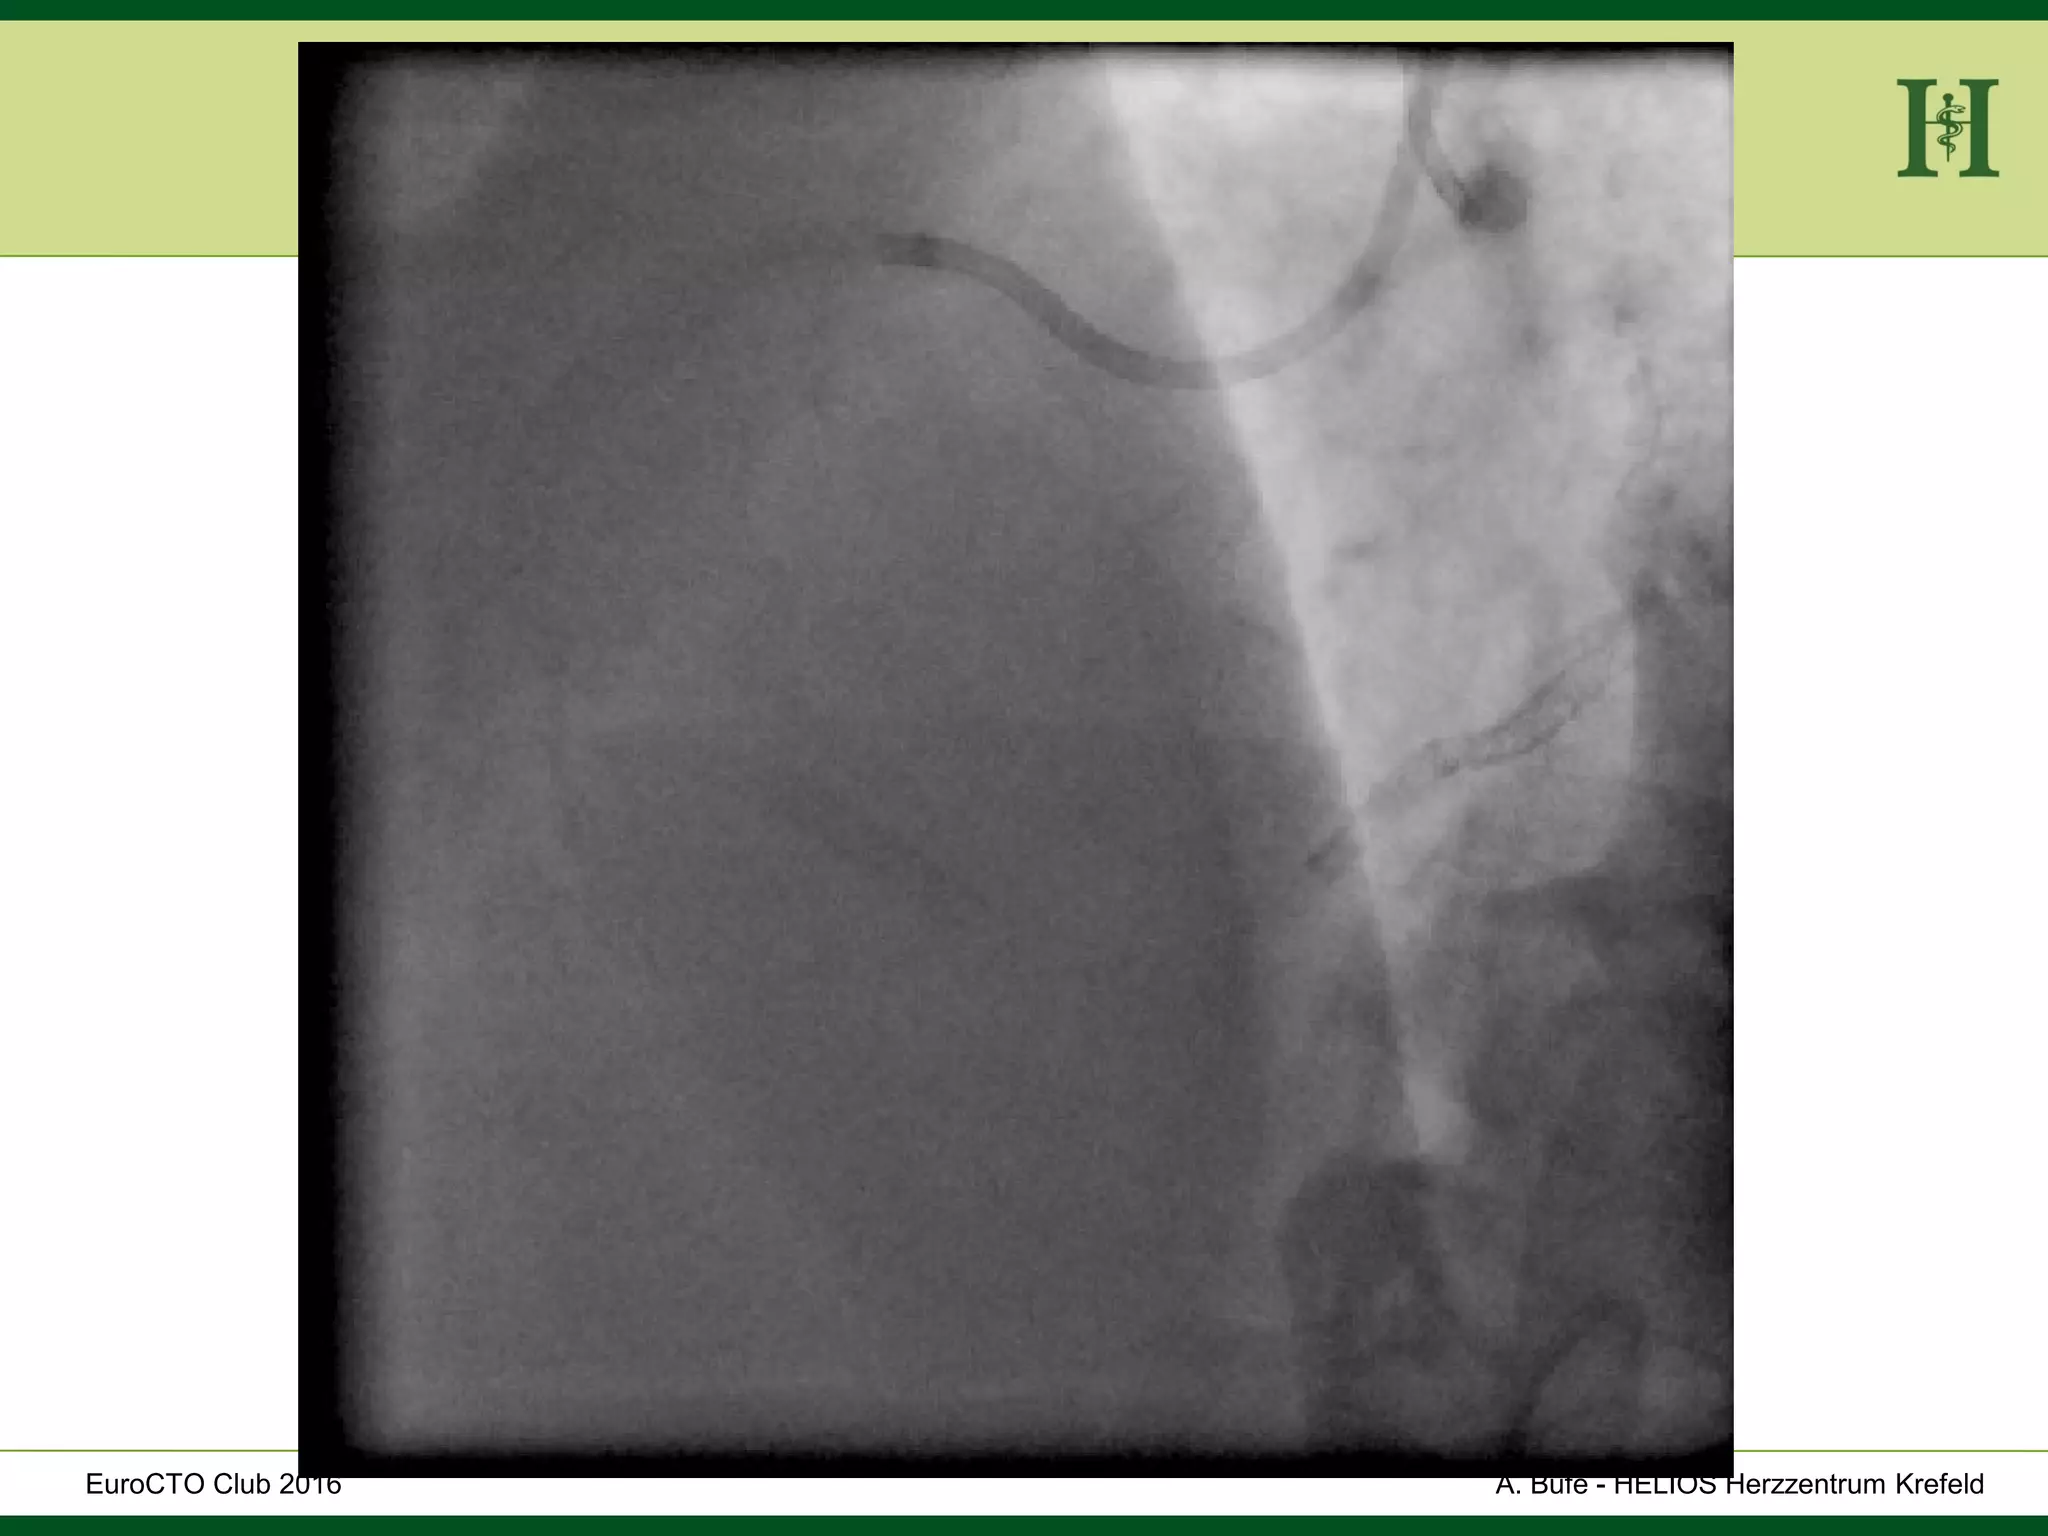

Male Patient, 55 years old

History:

 PCI 2015 with DES in LAD and in proximal RCA and

in PLD

 Angina pectoris CCS III for 7 months

 170cm, 75Kg

 RF: HLP, hypertension, smoking, HLP, familiy history

 Echo: Normal LV-Function, EF 65%

 Ischaemia inferior (MRI)